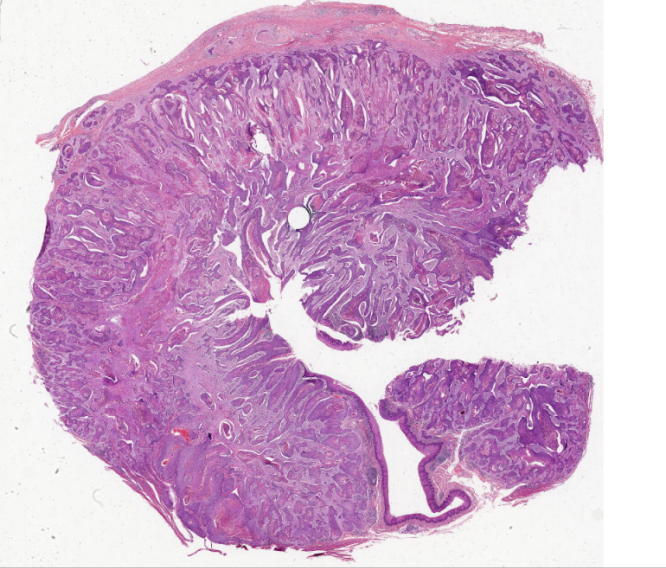

低倍镜观察:观察食管壁四层结构,即黏膜、黏膜下层、肌层和外膜。1、 黏膜:上皮为复层扁平上皮。

固有层突入上皮基底部形成乳头,有些地方因切面关系,乳头似在上皮内。黏膜肌层是一层纵行的平滑肌,

在食管横断面上肌细胞呈横断面。2、 黏膜下层:为疏松结缔组织,呈粉红色,纤维比较粗大,除细胞外,

还有较大的血管。此外,此层可见有黏液性的复管泡状的食管腺。3、 肌层:该片取自食管上三分之一部分,

为骨骼肌。可分为两层,两层之间的结缔组织内有肌间神经丛。

1.全景图

2.管壁四层